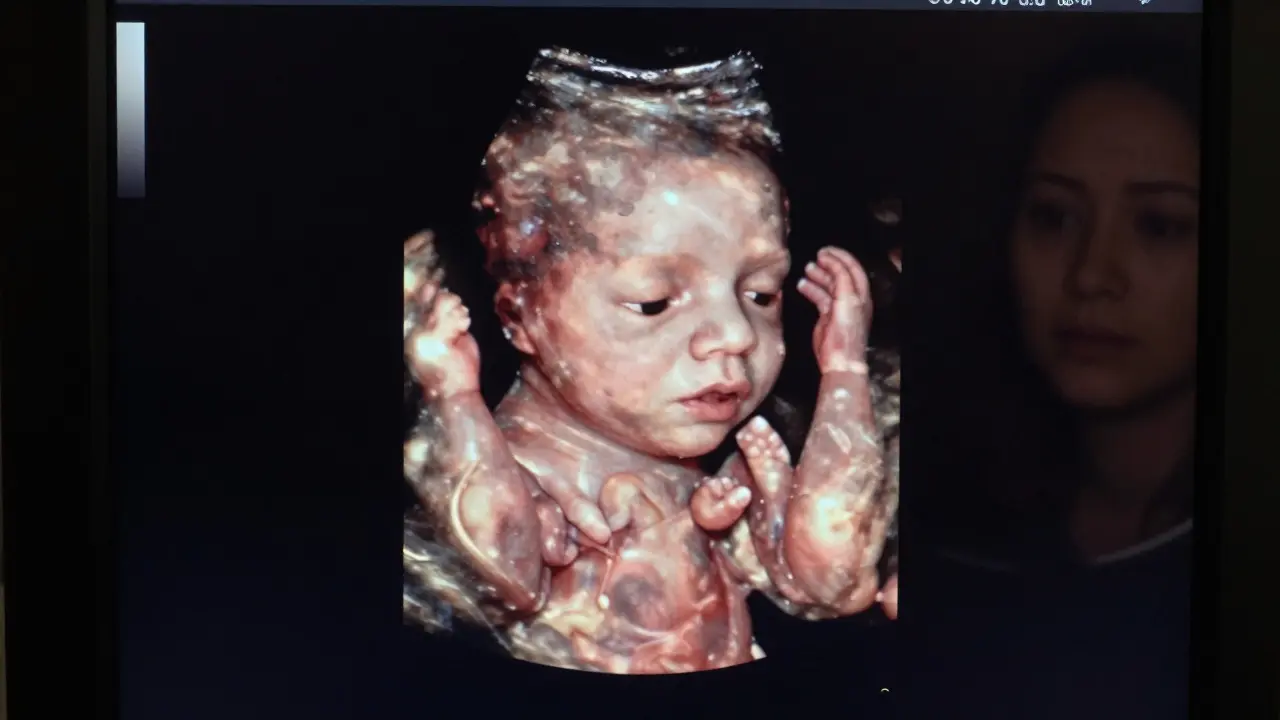

Na začátku těhotenství je plod příliš malý, aby bylo možné vidět všechny důležité struktury. Do 12. týdne se dělá tzv. národní screening, kde se kontroluje tloušťka krku a zda je přítomen nosní kost. To je jen začátek. Až kolem 20. týdne má plod dostatečnou velikost, aby bylo možné vidět srdce, mozek, ledviny, žaludek, ruce, nohy, prsty, chodidla, pohlaví a dokonce i výraz na obličeji. V této fázi je také možné přesně změřit růst a odhadnout hmotnost plodu.

Detailní snímek plodu ve 20. týdnu těhotenství s viditelnými orgány jako srdce, mozek a končetiny.